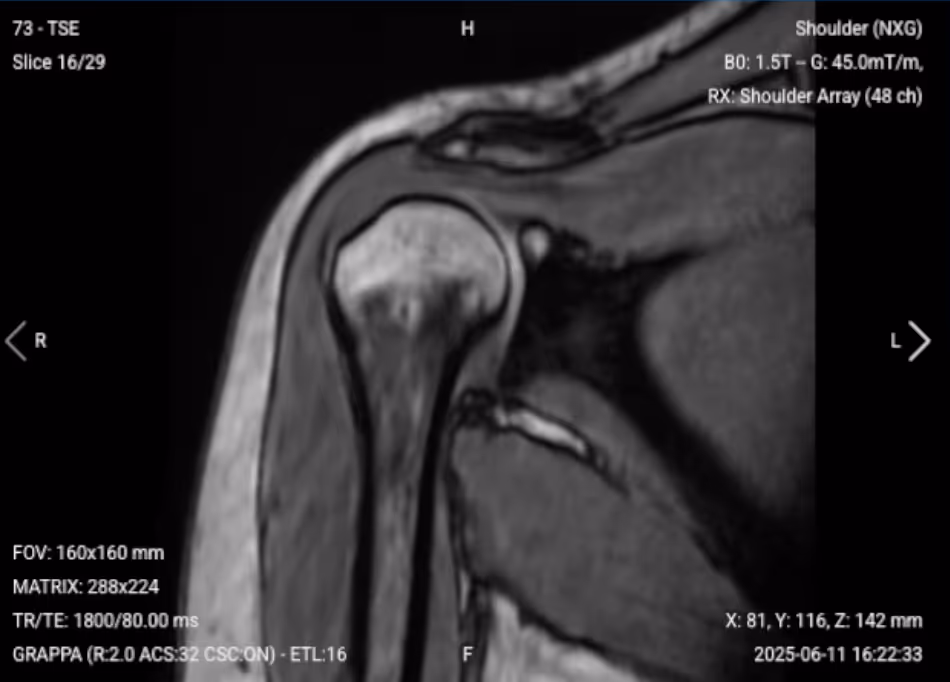

T1-weighted imaging makes fat appear bright and fluid dark. This contrast is ideal for fat-rich tissues and structural abnormalities. T1 shows anatomical structures clearly since it helps us see where different solid tissues like muscle and fat meet.

In shoulder MRI, T1 sequences are valuable for evaluating bone marrow pathology, fatty infiltration of muscles, and overall anatomical structure. T1 contrast helps identify bone marrow changes, muscle atrophy, and provides baseline anatomy for comparison with other sequences

✅ Sagittal T1 of the Shoulder – Correct Image Example:

Things to Look for in Sagittal T1: